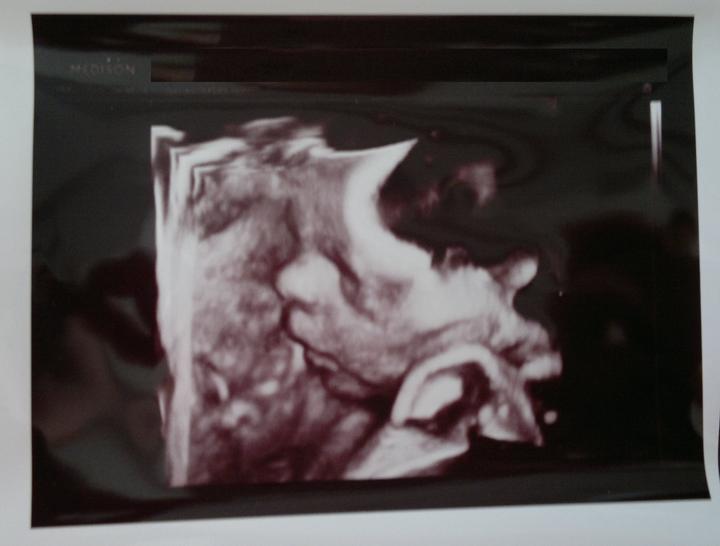

Jáchym Pavel Kolařík - 2. těhotenství

Termín porodu dle PM - 29. 8. 2014

( porod byl skutečně 24. 8. 2014 )